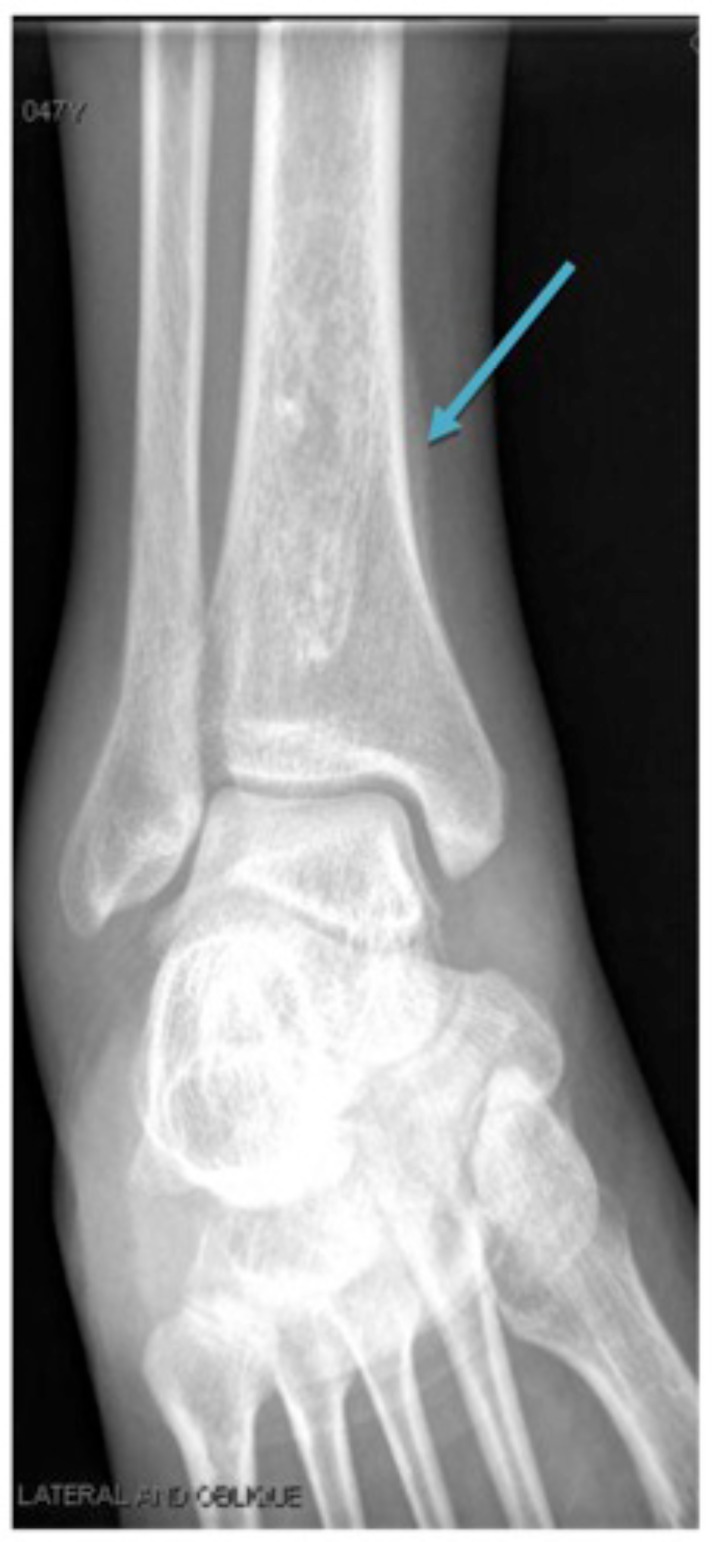

我们报告了一例47岁的非裔美国女性,她有15包年的烟草使用和大量酒精使用,表现为关节炎,并被发现有阳性的抗核抗体(ANA)、抗双链DNA抗体(抗dsdna)和抗干燥综合征相关抗原a和抗原B(抗ssa和抗ssb)。她随后被发现有肺腺癌合并肥厚性肺骨关节病(HPO)。这是一例肺腺癌患者的抗核抗体阳性和关节炎,可被误诊为系统性红斑狼疮。

We present a case of a 47 year-old African American female with 15 pack-years of tobacco use and heavy alcohol use who presented with arthritis and was found to have a positive antinuclear antibodies (ANA), anti double stranded DNA antibodies (anti-dsDNA), and anti-Sjogren's syndrome-related antigen A and antigen B (anti-SSA and anti-SSB). She was subsequently found to have a lung adenocarcinoma associated with hypertrophic pulmonary osteoarthropathy (HPO). This demonstrates a case of positive antinuclear antibodies and arthritis in a patient with lung adenocarcinoma, which can be falsely diagnosed as systemic lupus erythematosus.